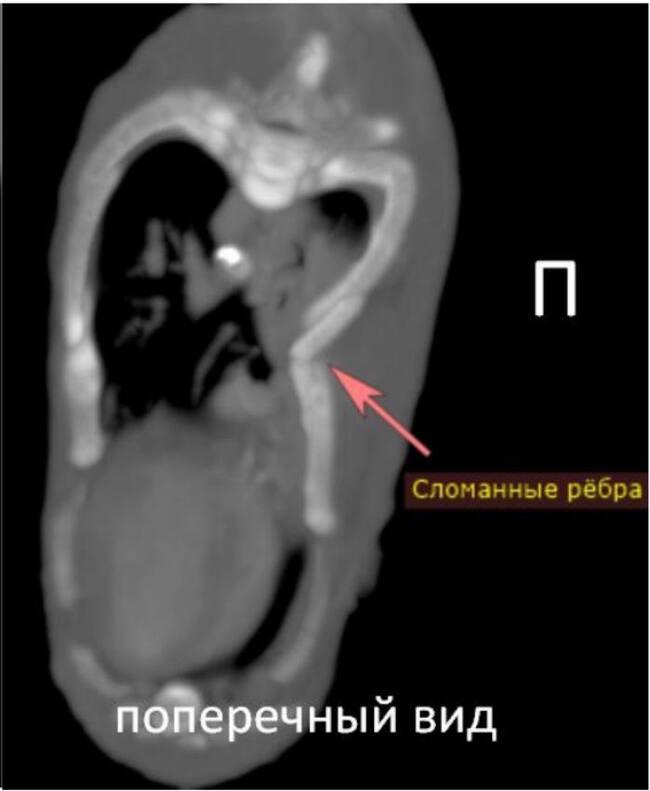

Я иногда пишу про компьютерную томографию животным, но сфера узкая и находит мало откликов в сердцах коллег. Хотя по-моему это фантастически интересно и очень красиво. Наткнулась на пост с интересными рентгеновскими снимками и подумала, а вдруг, вдруг кому-то и мои снимочки будут интересны?

К делу:

Болезнь собаки мясника - околонародное название для алиментарного гиперпаратиреоза (вторичного пищевого гиперпаратиреоза) Заболевание связано с вымыванием кальция из костей и органов из-за нарушения соотношения количества кальция и фосфора в крови и развивается при несбалансированном кормлении животных (как правило, при кормлении одним мясом: поэтому и «болезнь собаки мясника». Мяснику очень удобно кормить сабачку обрезью и прочим, а потом не затруднительно заменить на новую собаку) (это я не обижаю никак мясников, это я поясняю смысл термина).

Так вот, недостача кальция в пище приводит к тому, что организм начинает компенсировать её своими силами, и начинает вымывать кальций из мест депонирования в организьме. Из кишечника, других органов, из костей.

Это в свою очередь приводит к тому, что кости становятся визуально полупрозрачными, физически непрочными и ломкими. Такие зверята начинают случайно ломаться в разных местах, деформироваться и страдать от боли. На приёме как правило оказывается неходячее и очень болящее животное.

Возможности вылечить зависят от того, где, сколько раз и насколько неудачно пациент сломался. И от возможности донести до владельцев необходимость сбалансированного питания.

Немножко сканов котенка, которого кормили мясом. Кости становятся хрупкими и могут буквально складываться, как бумага (особенно позвонки и кости лап. Часто такие животные, если их удается полечить, имеют аномально изогнутый позвоночник и кривые другие кости):

А тут рентгеновский снимок, на котором хорошо видно снижение плотности костей черепа. Зубы яркие, а остальные кости на их фоне прямо таки очень ненавязчивые: